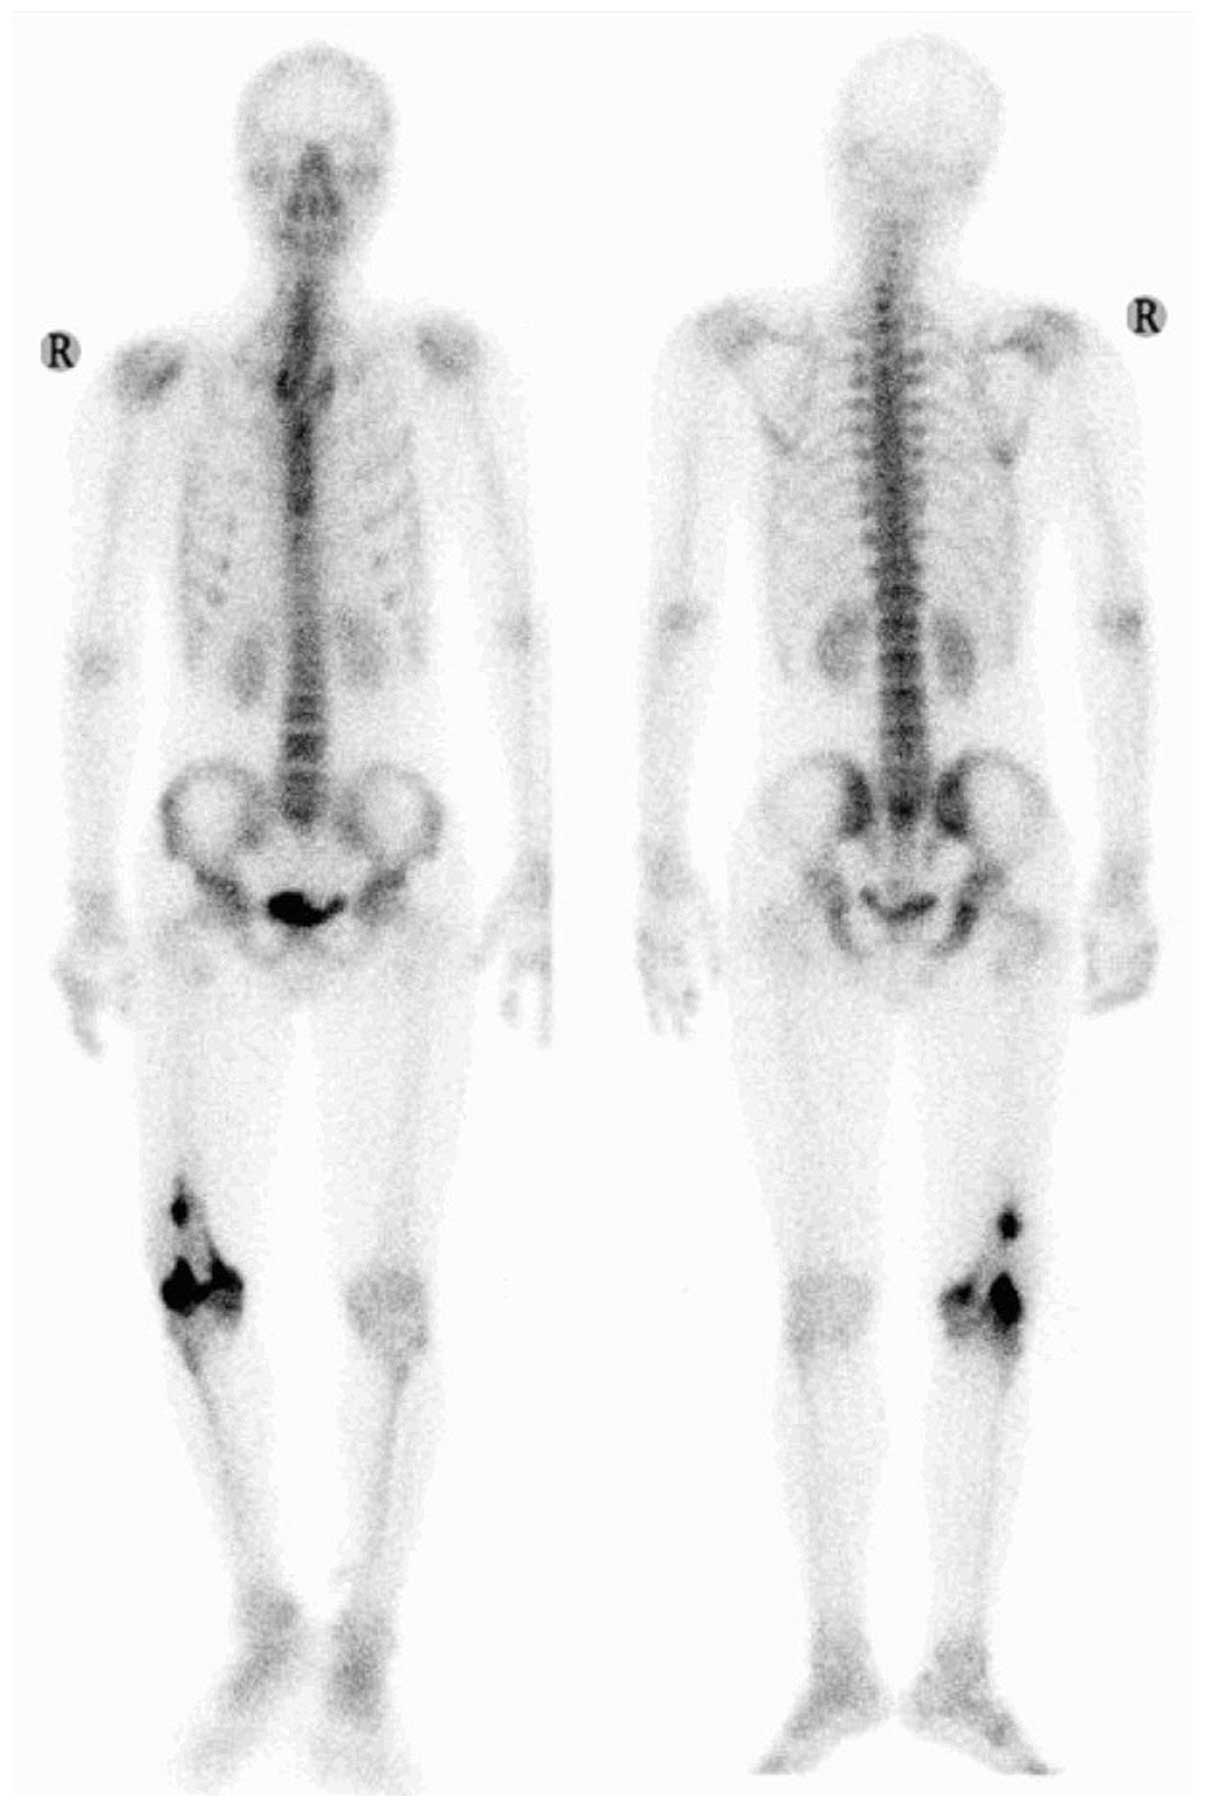

bone invasion. An emission computed tomography (CT) bone scan

demonstrated an abnormal isolated concentration of radioactive

agent (used for bone imaging) at the femoral site, which revealed

that no distant metastases had occurred (Fig. 3). Chest CT did not demonstrate any